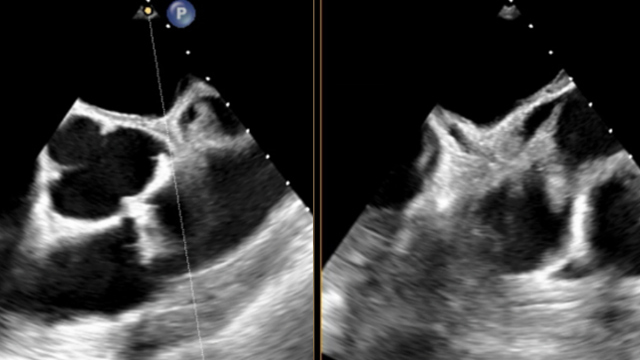

A 77-year-old male with atrial fibrillation and chronic kidney disease presented with symptomatic severe atrial tricuspid regurgitation.He underwent implantation of two TriClip XTW devices (antero-septal and postero-septal) under general anesthesia, guided by transesophageal echocardiography (TEE).